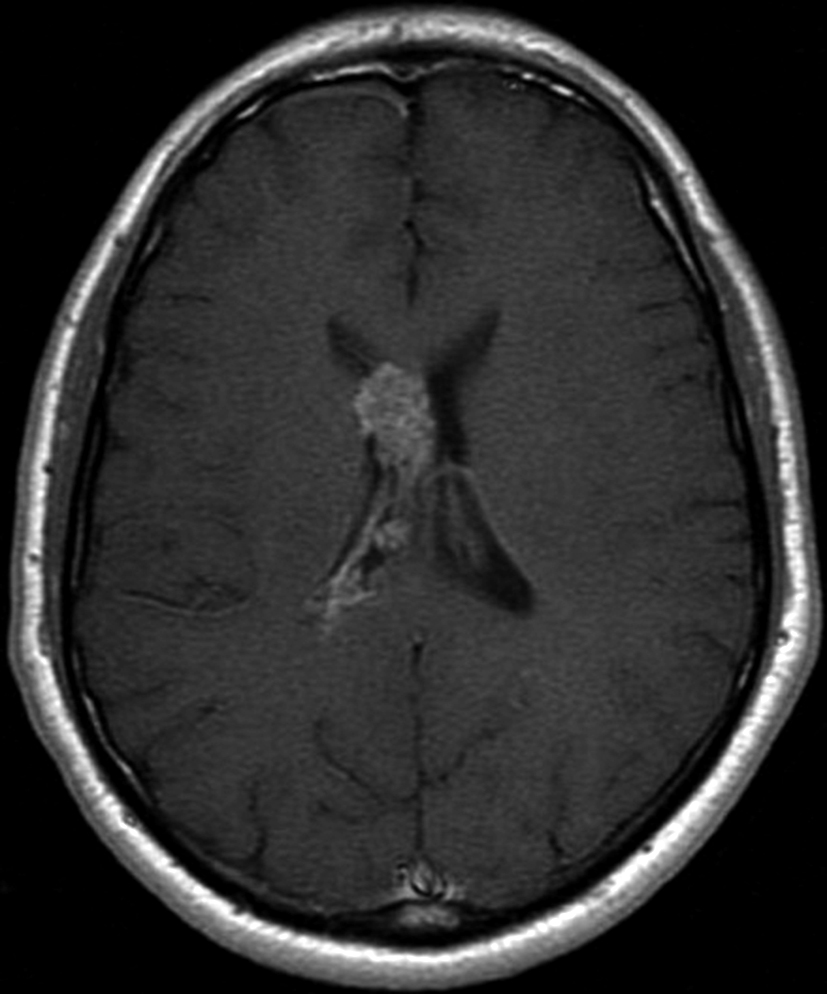

Con los hallazgos tomográficos, no se efectúan planteos diagnósticos y se realiza una resonancia magnética con la finalidad de obtener más datos semiológicos en busca de una aproximación diagnóstica. Se realizó el estudio por medio de secuencias T 1, FSE T 2, FLAIR, SWI y Difusión, en cortes axiales, FSE coronal y sagital T 1. Se realiza la administración de gadolinio DTPA en los tres planos. Se evidencia la lesión bien definida a nivel del ventrículo lateral derecho, que involucra al tronco del cuerpo calloso (Figura 2- C y 3- B). Presenta intensidad de señal heterogénea en secuencias T1 y T2 (Figura 3 y Figura 4). En secuencia ecogradiente se observa una señal marcadamente hipointensa y heterogénea, con un halo hipointenso bien definido (Figura 2- C). No presenta realce significativo tras la administración de Gadolinio (Figura 2- B) y en la secuencia de difusión no presenta restricción.

Figura 2 Resonancia magnética.

a) Imagen axial T1, lesión intraventricular con intensidad de señal heterogénea.

b) Tras la administración de Gadolinio no presenta realce significativo.

c) Imagen axial en secuencia ecogradiente donde se evidencia la lesión hipointensa y heterogénea. Se observa la extensión de la lesión al cuerpo calloso.